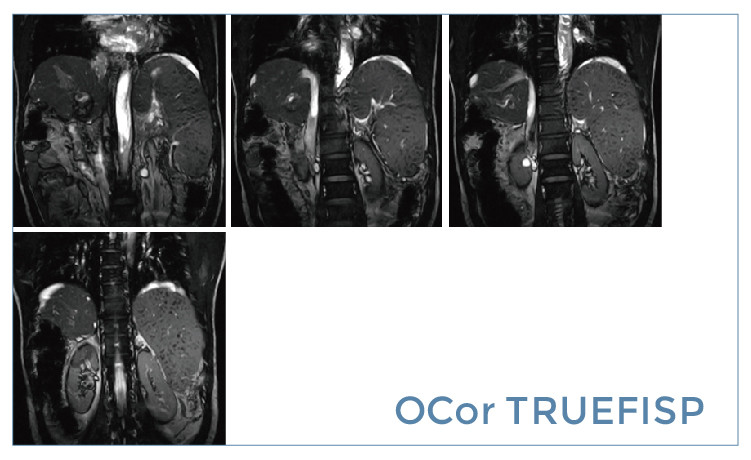

【朗润影像档案】20190517磁共振影像病例结果讨论